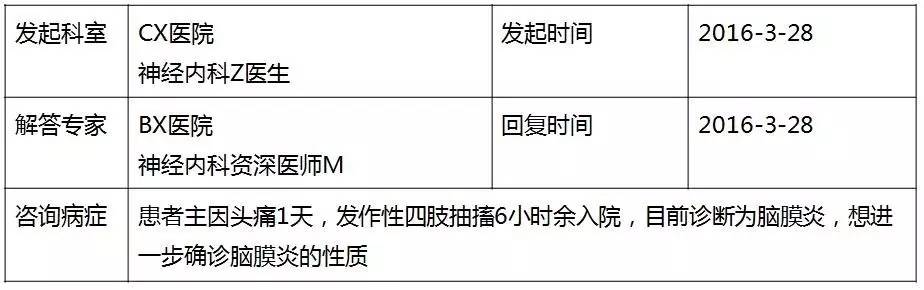

【病例分享】中枢神经系统感染1例

患者:男性,36岁,主因“头痛1天,发作性四肢抽搐6小时余”于2016年3月24号入院。

咨询目的:

目前考虑中枢神经系统感染,进一步明确病因,帮助分析一下哪种可能性大?下一步检查及治疗?

基础信息